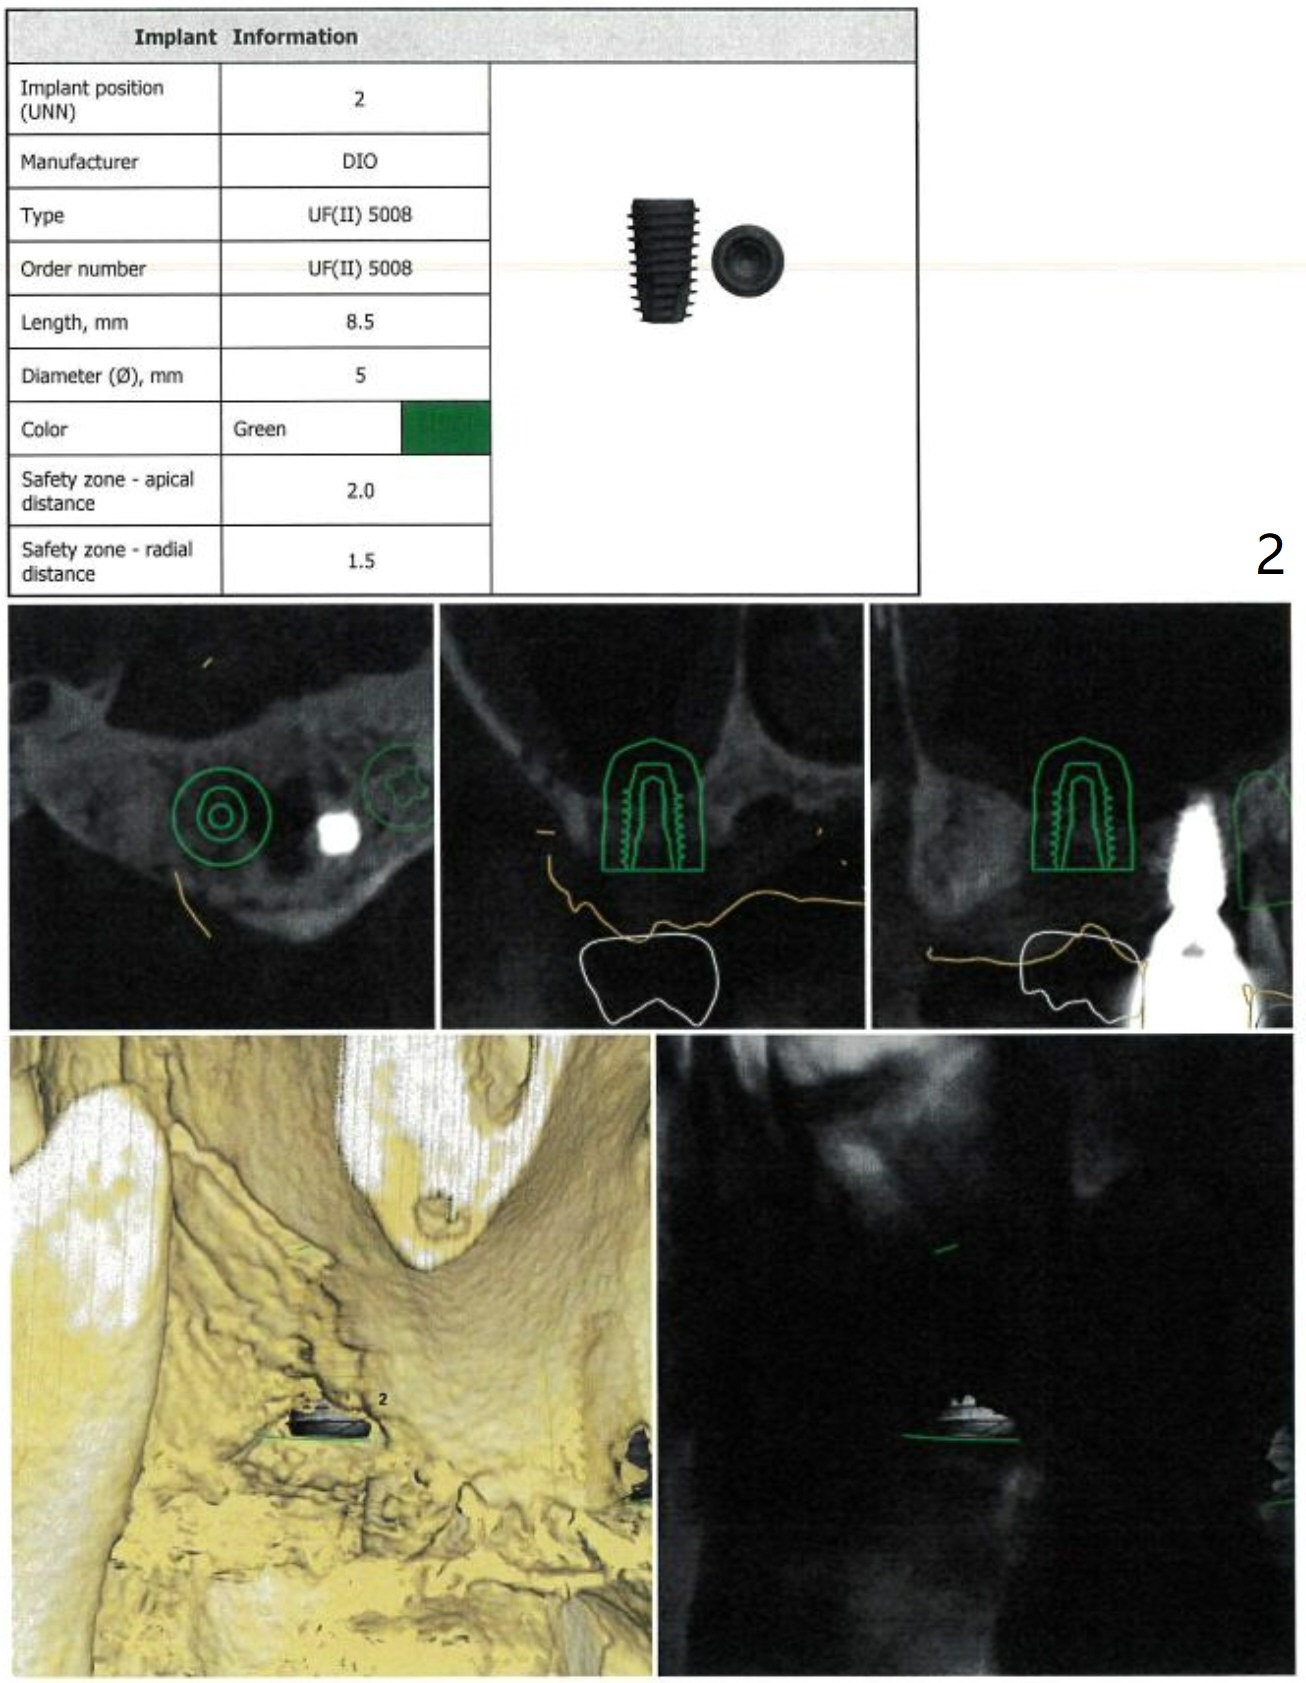

Two Implants

In fact the patient agrees to have 2 implants (#2 and 4) to be placed at the same time.